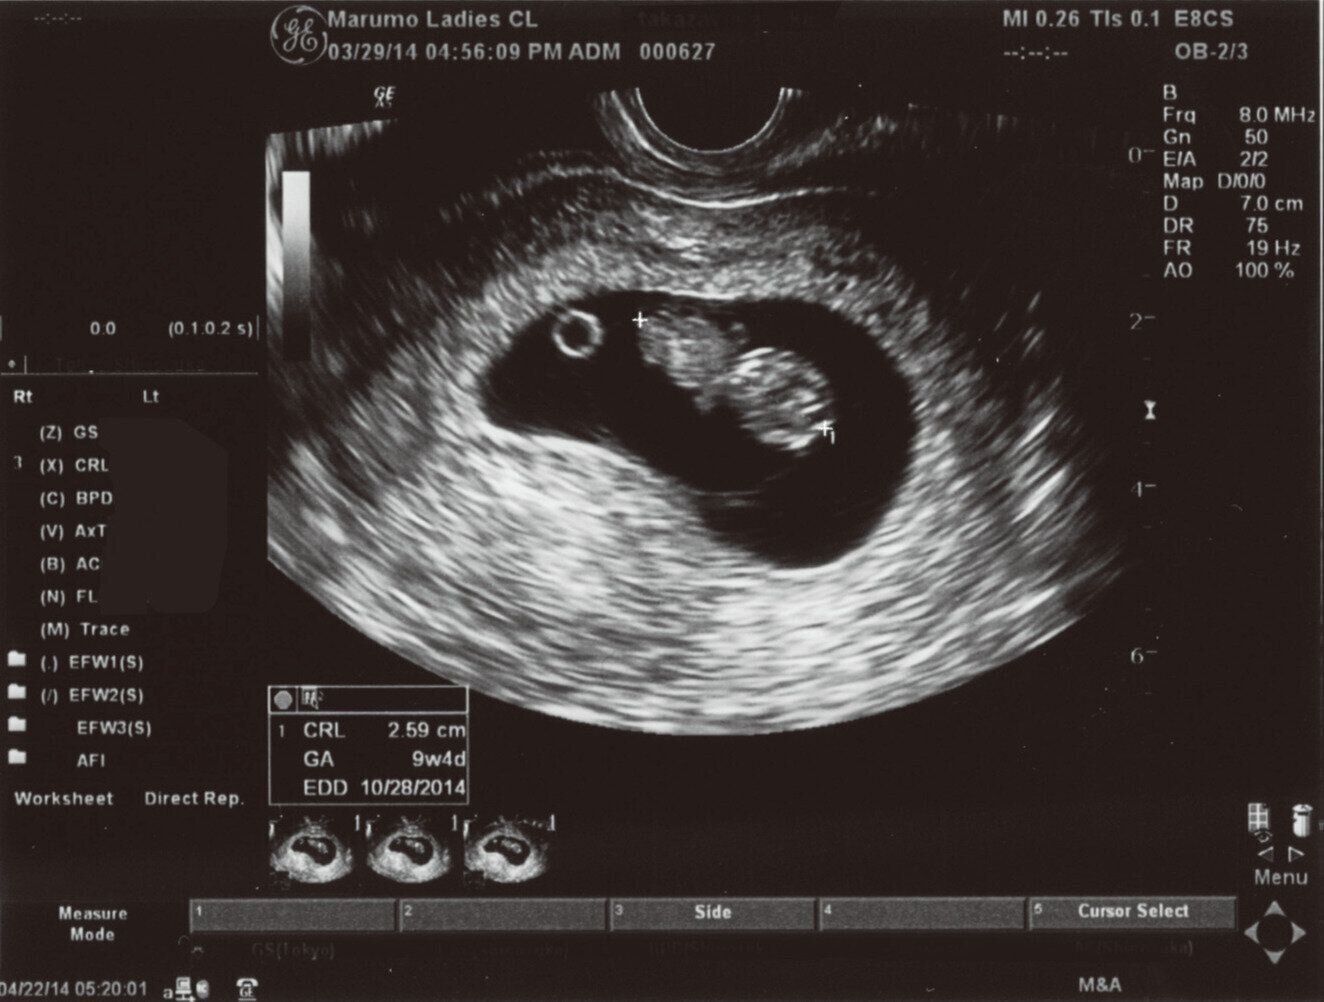

3. 【医師監修】産科医がビジュアルで解説します!「超音波写真(エコー写真)の見方」ガイド